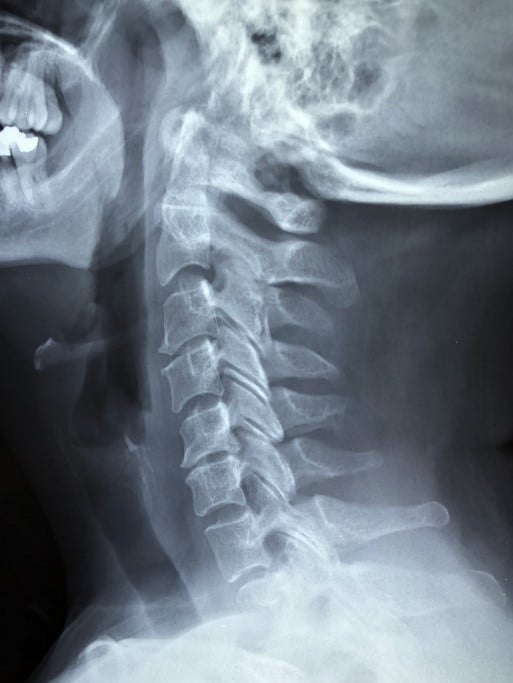

El clásico golpe por detrás parado en un paso de peatones o en un semáforo, o en una retención de tráfico.

Tienes pocos daños materiales y sientes molestias en el cuello.

Te vas a casa y pasas unos días reposando y tomando analgésicos, pensando que es suficiente para que tus “molestias” desaparezcan.

Pero van pasando las horas y te encuentras peor, porque esa molestia se convierte en dolor o en una limitación de movilidad de tu cuello.

Finalmente decides acudir al médico, y te diagnostican una lesión en el cuello.

Vas a tener que reclamar a la aseguradora contraria una indemnización por latigazo cervical.

O por un esguince o cervicalgia postraumática.

O una inflamación en el cuello con mareos y náuseas que impide a los rehabilitadores manipularte la zona y debes esperar para empezar el tratamiento.